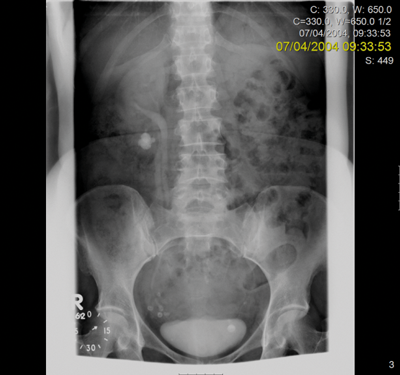

Preoperative IVU and CT demonstrating very little overlying renal cortex in duplex system.

Seven years postoperatively. New left staghorn calculus and right-sided fragment demonstrated outside the kidney.